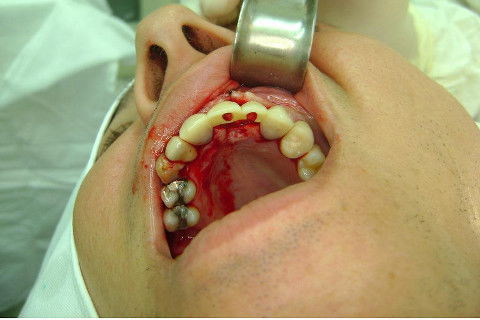

Cirurgia realizada hoje de manhã...No planejamento percebi medindo espessura do rebordo com especímetro que as medidas não estavam muito boas, ou o ideal, em torno de 4,5 a 5 mm ate´o terço médio do rebordo e melhorava no final, com 6 a 7 mm. Optei então por uma pequena expansão usando os expansores rosqueáveis. Aconteceu uma pequena fenestração na hora da fixação dos implantes, especialmente na região do 22 que fraturou o início da tábua óssea, mas não me preocupei porque não foi mais do que 2 mm de fratura em direção apical, o implante ficou infraósseo e com boa estabilidade (60 N no 21 e 40 N no 22). Esta fratura tb não deixou osso completamente solto, foi do tipo galho verde, deixei em posição e suturei normalmente. Só não fiz e nem estava planejado carga imediata mesmo, mais pelo motivo da oclusão inadequada do caso.

Fotos do caso